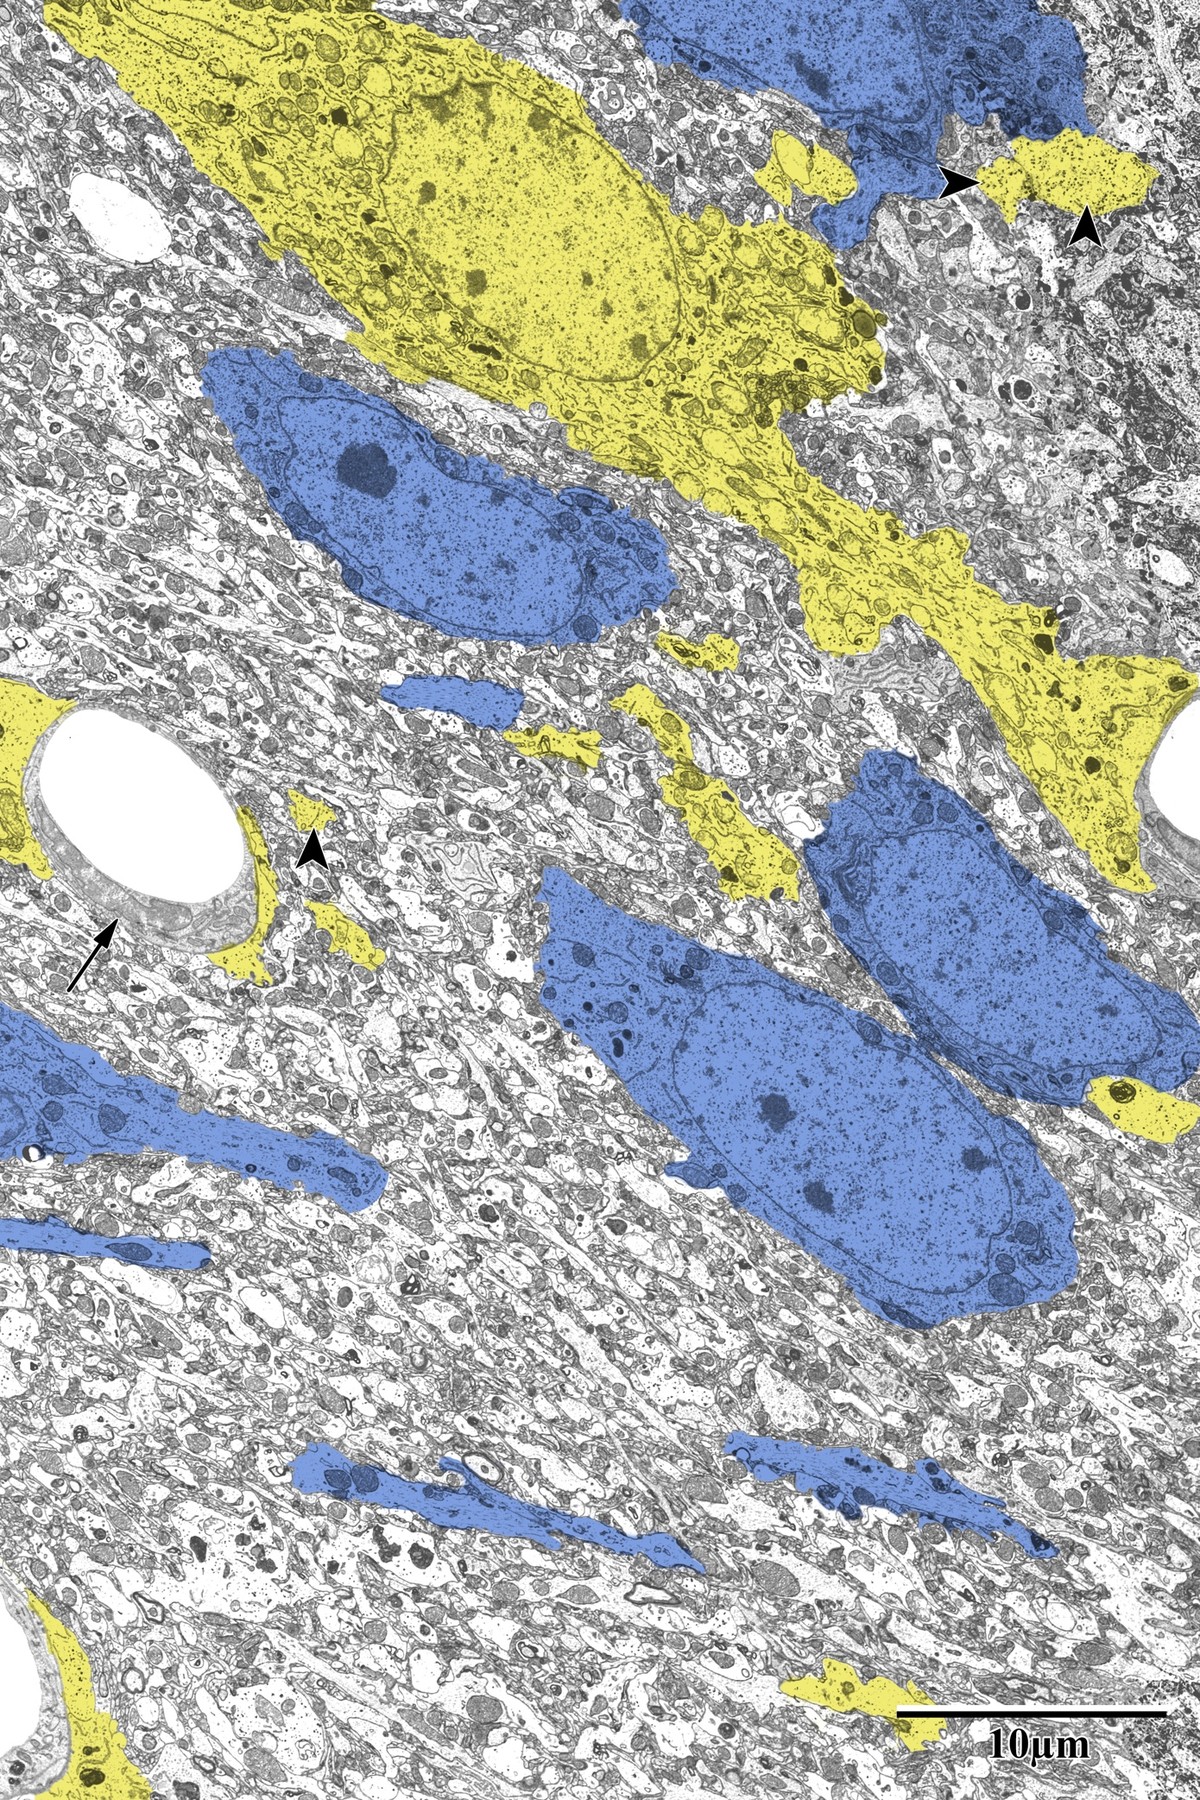

Astrocytic Inflammation & Mitochondrial Changes

Astrocytes responded dramatically to ischemic injury, showing increased process area and reactive morphology in the peri-infarct zone. Astrocytic processes were traced and pseudocolored yellow for quantification, revealing glycogen granule accumulation, swollen mitochondria, and extensive perivascular endfeet coverage around capillaries.

Reactive Astrocytosis

Pseudocolored astrocytes (yellow) surrounding neurons (blue) in peri-infarct zone

Peri-infarct zone: reactive astrocytes (yellow) surrounding pyramidal neurons (blue). Note the dramatically increased astrocytic coverage compared to control tissue, with microglia also visible. From Bayati, BSc Honours Thesis 2018.

Astrocytic endfeet around capillary with microglia

Astrocytic endfeet (yellow) surrounding a capillary in the peri-infarct zone. Lighter mitochondria (arrows) and glycogen granules (arrowheads) are identifying features. Microglia visible in close proximity, suggesting active inflammation. From Bayati, BSc Honours Thesis 2018.